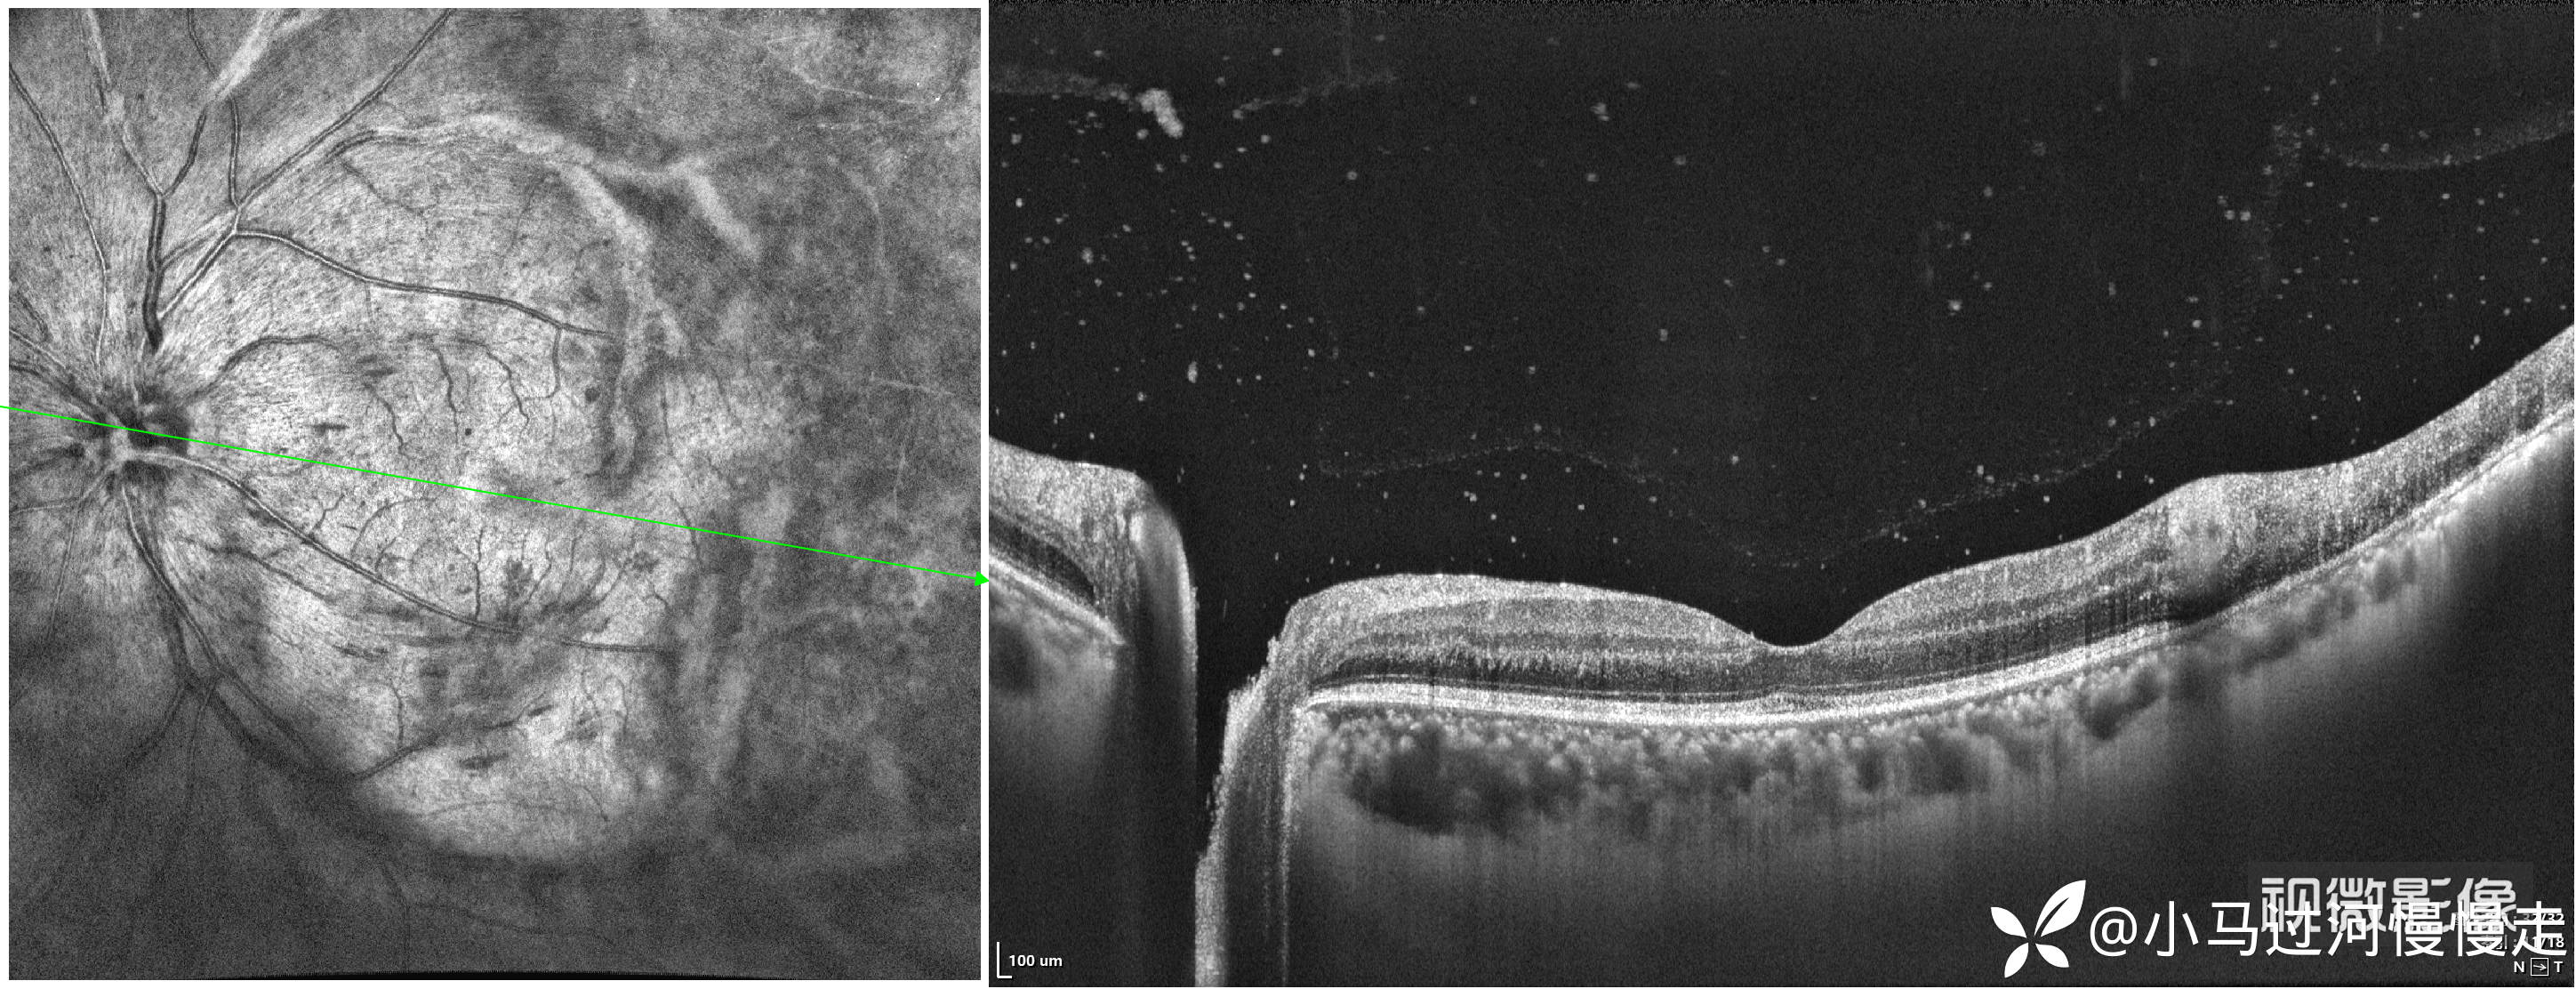

患者是HIV感染者,就诊时外院已经确诊了AIDS。右眼底正常,左眼底表现为霜枝样静脉炎及颞侧"番茄炒蛋"样病变,病变中心可见坏死灶:

当时正在试用视微SSOCT,记录了左眼颞侧病变的影像。